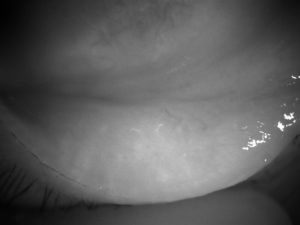

Dry Eye Examination includes assessments of:

- Tears meniscus height

- Tears volume